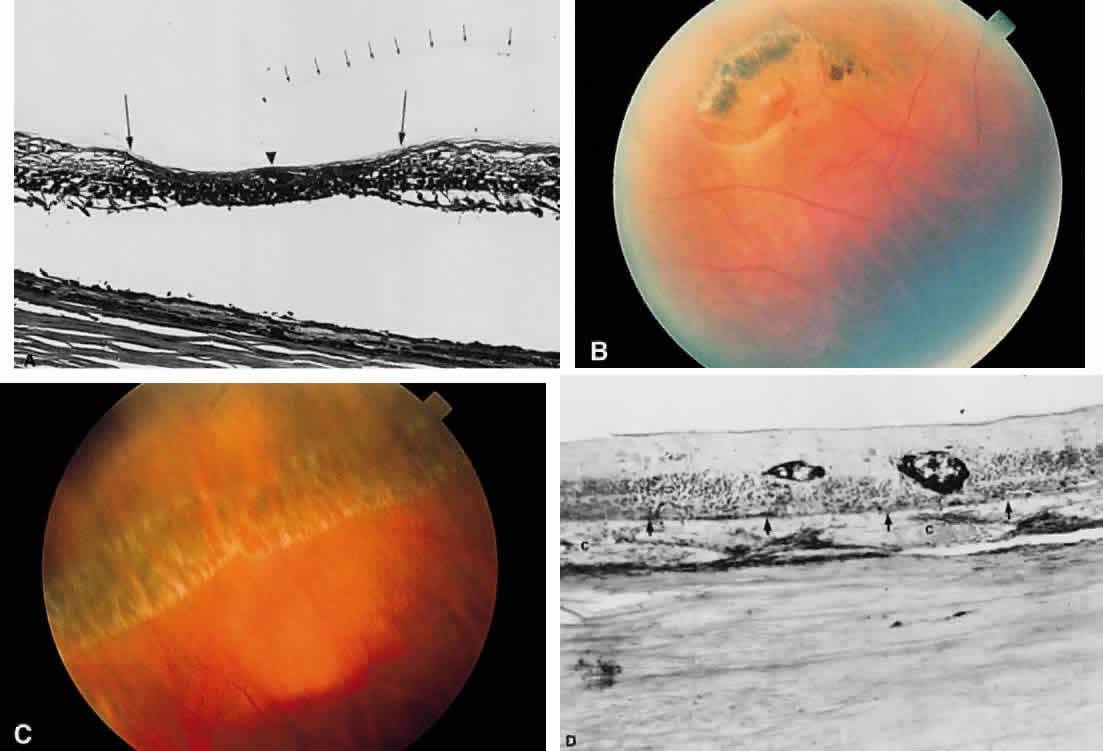

and has sharp borders (Fig. 13).  Fig. 11. A. Section of retina with hemorrhage in the nerve fiber layer (between the two large arrows). Notice that the limits of the hemorrhage are not clearly defined, since

scattered red blood cells can be seen to the right of the right-hand

large arrow. This histologic picture corresponds to a clinically observed

fame-shaped hemorrhage with an indistinct border. The detached

posterior hyaloid is marked by four small arrows. B. Fundus photograph of nerve fiber layer hemorrhage. They are oriented parallel

to the plane of the internal limiting membrane. Because of their

dispersal within the ganglion cell layer, the borders are “feathery” (flame

shaped). Fig. 11. A. Section of retina with hemorrhage in the nerve fiber layer (between the two large arrows). Notice that the limits of the hemorrhage are not clearly defined, since

|

Fig. 12. Section of the eye showing subretinal hemorrhage. (Courtesy of Ralph C. Eagle Jr, MD, Philadelphia, PA) Fig. 12. Section of the eye showing subretinal hemorrhage. (Courtesy of Ralph C. Eagle Jr, MD, Philadelphia, PA)

Fig. 13. A. Fundus photograph of a subpigment epithelium hemorrhage superotemporal

to the disc secondary to a macroaneurysm. Notice its dark color and sharp

border. The central portion of the hemorrhage has extended through

the sensory retinal to the subinternal limiting membrane area. B. Fluorescein angiography showing the retinal vessels overlying the deep

hemorrhage but obscured by the central extension anteriorly. (B, courtesy of William Tasman, MD, Philadelphia, PA) Fig. 13. A. Fundus photograph of a subpigment epithelium hemorrhage superotemporal

to the disc secondary to a macroaneurysm. Notice its dark color and sharp

border. The central portion of the hemorrhage has extended through

the sensory retinal to the subinternal limiting membrane area. B. Fluorescein angiography showing the retinal vessels overlying the deep

hemorrhage but obscured by the central extension anteriorly. (B, courtesy of William Tasman, MD, Philadelphia, PA)

|